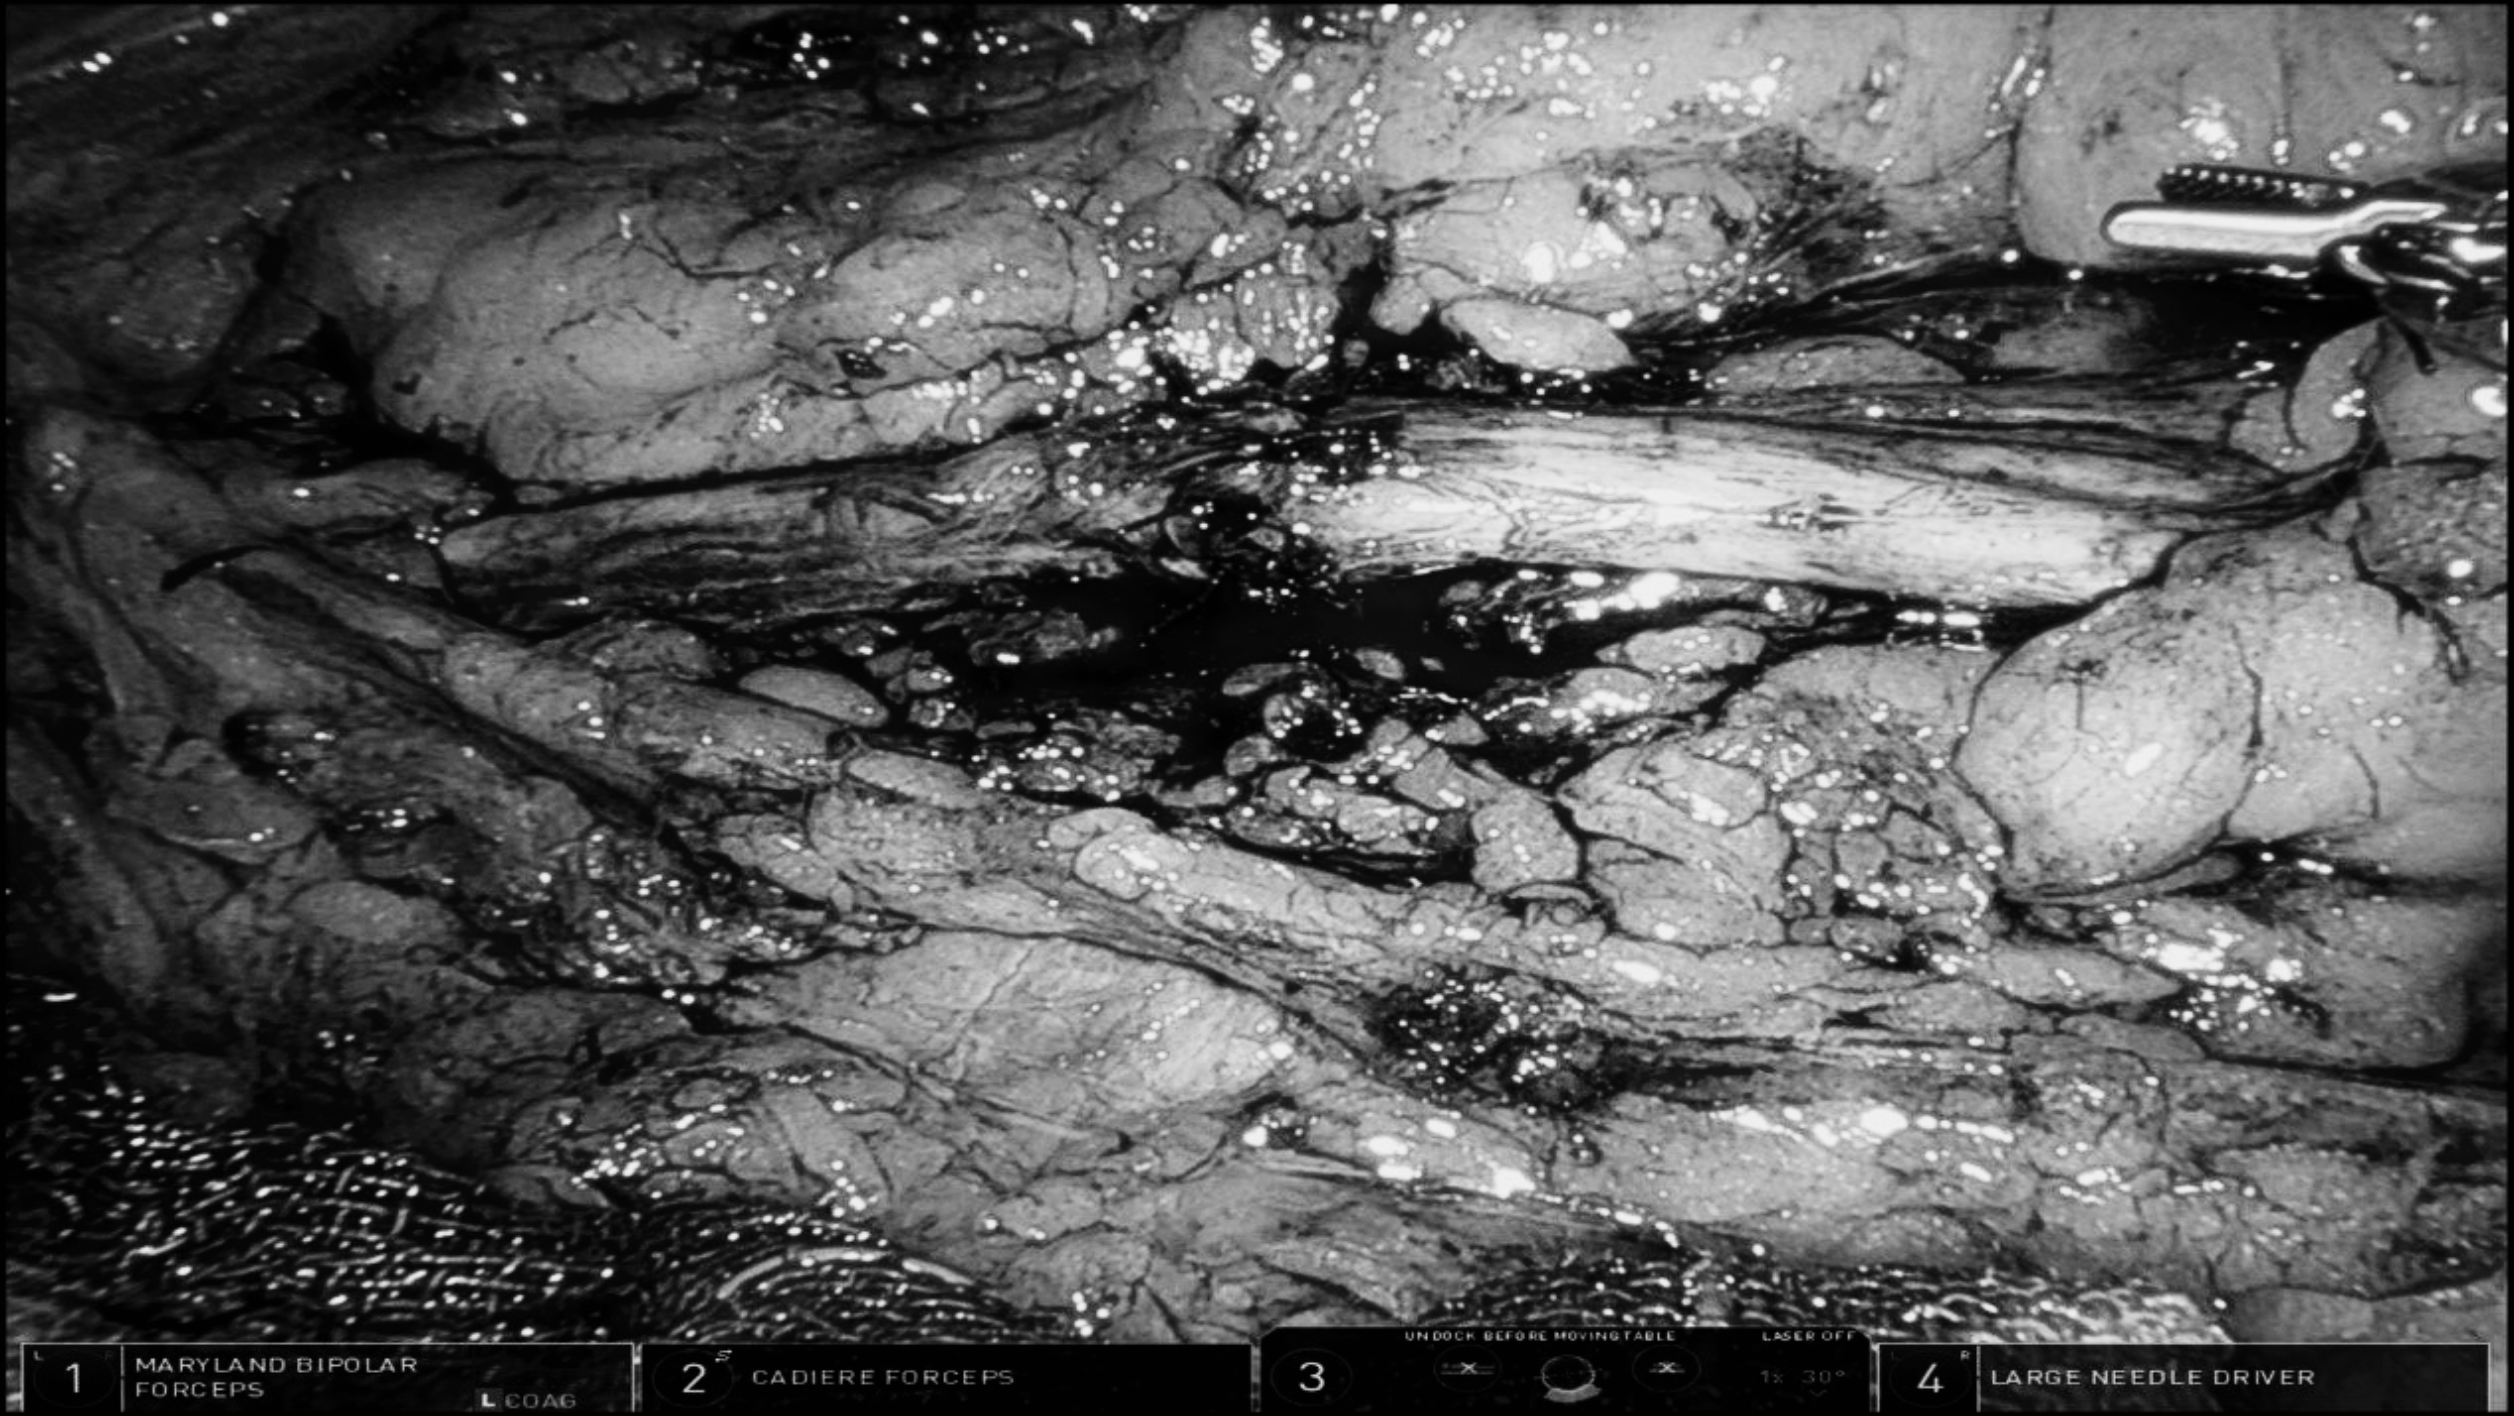

手术方式:机器人辅助腹腔镜右输尿管离断吻合+取石术

2. 术前MRU显示输尿管狭窄约2cm左右,手术初步计划颊粘膜补片,术中松解输尿管后离断吻合,张力不大,荧光造影显示吻合口两端血供良好。

3. 此类手术难点在于吻合严密,小针细线,保护血供,防止再次狭窄。